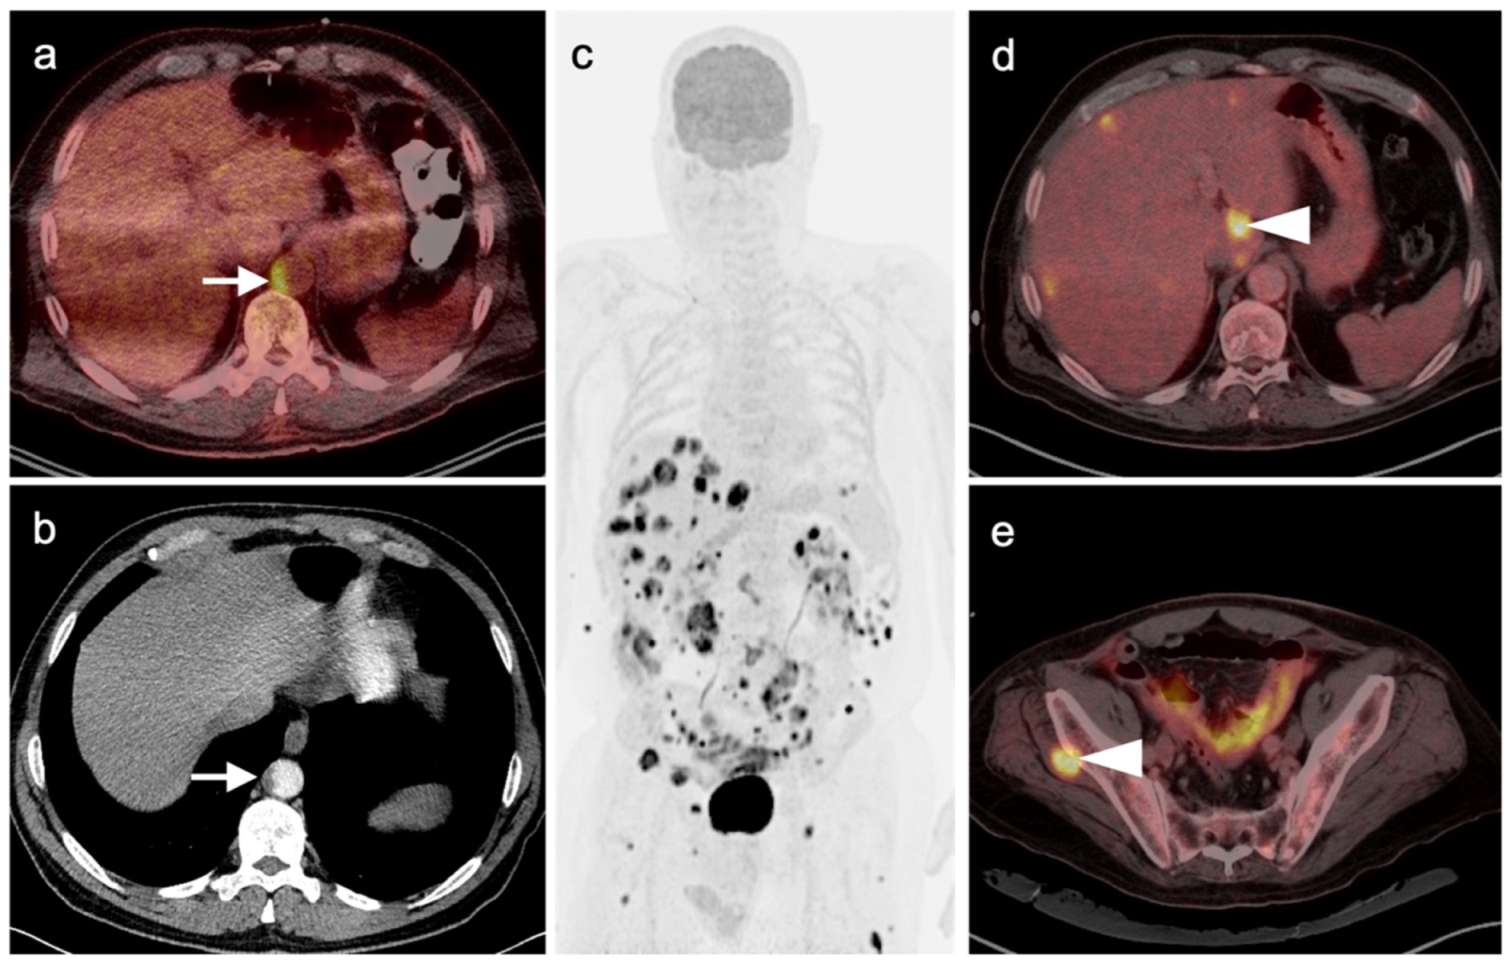

2.3.3. Mucosal Melanoma

- Goerres, G.W.; Stoeckli, S.J.; Von Schulthess, G.K.; Steinert, H.C. FDG PET for Mucosal Malignant Melanoma of the Head and Neck. Laryngoscope 2002, 112, 381–385. [Google Scholar] [CrossRef]

- Murphy, G.; Hussey, D.; Metser, U. Non-cutaneous melanoma: Is there a role for18F-FDG PET-CT? Br. J. Radiol. 2014, 87, 20140324. [Google Scholar] [CrossRef] [Green Version]

- Falch, C.; Mueller, S.; Kirschniak, A.; Braun, M.; Koenigsrainer, A.; Klumpp, B. Anorectal malignant melanoma: Curative abdominoperineal resection: Patient selection with 18F-FDG-PET/CT. World J. Surg. Oncol. 2016, 14, 185. [Google Scholar] [CrossRef] [Green Version]